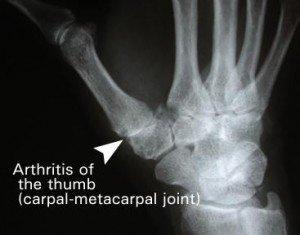

Thumb Basilar Joint Osteoarthritis

Osteoarthritis of the hand most commonly involves the thumb basilar joints and sometimes also the finger distal interphalangeal joints. During the early stages of arthritis, people have pain and tenderness about the base of the thumb, which limits their strength and use of the thumb. As the arthritis progresses, people lose motion, and the thumb basilar joint may become unstable and subluxate. With advanced osteoarthritis, the thumb basilar joint becomes prominent, painful and stiff, sometimes with compensatory hyperextension of the adjacent thumb metacarpal- phalangeal joint.